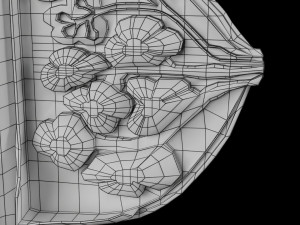

Breast anatomy histology detailed labelled precise to scale model 3D Модель

This is a 1:1 scaled model of right breast cut opened in sagittal plane to reveal its internal antomy and histology (schematic). The deeper parts and fascial layers are also depicted to give a very detailed approach to the model. The full layers starting from skin, nipple areola, till intercodtal muscles and ribs are also depicted.